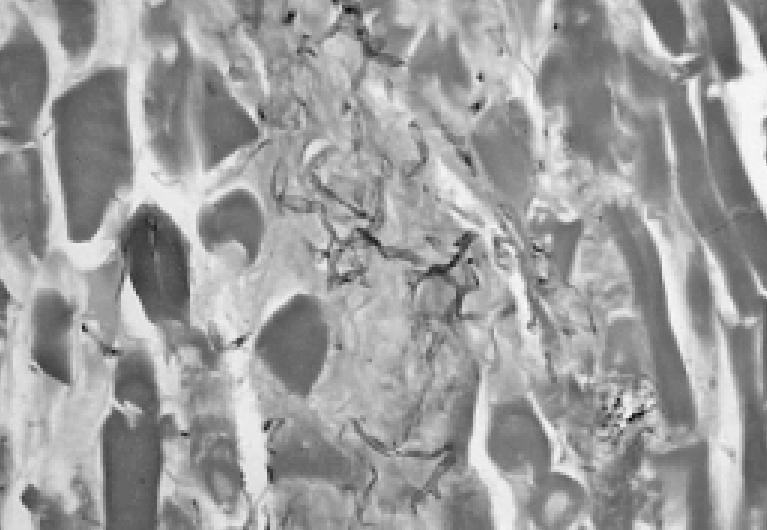

JENNIFER M. GILSOUL, MD: We received many specimens from this patient in September 2000 and the subsequent months. They all showed the same finding: massive necrosis throughout the tissue. Another prominent feature was vessel damage and thrombosis, also seen throughout the tissue (Figure 3). Figure 4 demonstrates the pathogen: 2 vessels are surrounded and invaded by fungal hyphae. At high magnification, fungal invasion of the wall can be seen. The fungi have broad, ribbonlike, twisted hyphae with nonparallel walls that come in and out of the plane of section. The fungus branches at right angles (Figure 5). Unlike many other fungi, it only stains lightly with Gomori methenamine–silver stain. It stains better with periodic acid–Schiff stain.

Fungal hyphae branch at right angles within the necrotic muscle.

These features are characteristic of fungi in the class Zygomycetes, which cause zygomycosis or mucormycosis, as it is commonly called. These fungi cause rhinocerebral, pulmonary, gastrointestinal, cutaneous, or disseminated infection in predisposed individuals, such as those with diabetes, hematologic malignancies, or burns. The fungus invades the vessels and damages the walls, causing thrombosis and then infarction of the tissues. Whether significant inflammation is present depends on the immune status of the patient. The most common agents in human infection comprise the genera Rhizopus, Mucor, Absidia, Apophysomyces Cunninghamella, Rhizomucor, and Saksenaea. By far the most common is Rhizopus. The fungus can't be classified solely from tissue sections because the hyphae all look the same. The fungus must be cultured to be identified accurately.